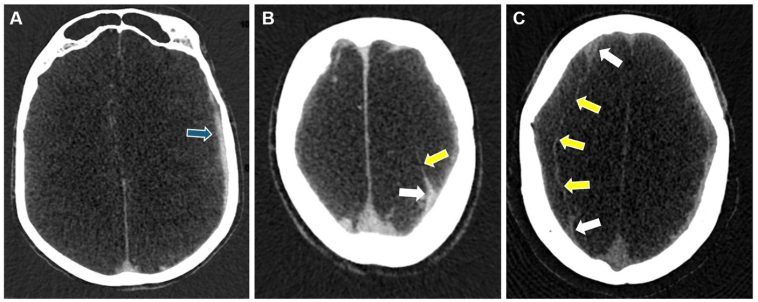

Advanced Imaging Techniques: Enhanced Visualization Amidst the Hidden Complexities

Accurate diagnosis is absolutely critical in the management of chronic subdural hematoma. While computed tomography (CT) remains the go-to imaging tool for a quick assessment, there are several challenges that call for a more nuanced approach. CT imaging, which typically shows a crescent-shaped collection of blood, can sometimes miss the finer details such as small or isodense hematomas, thereby complicating the diagnosis. Moreover, the internal architecture of the hematoma is often not fully appreciated on CT scans.

Magnetic resonance imaging (MRI) offers a more refined look, thanks to its superior soft-tissue resolution. With MRI, radiologists are better equipped to expose the septations and membrane structures that often serve as clues to the hematoma’s maturity and its propensity to recur. Modern MRI techniques, such as diffusion-weighted imaging, have added another layer of detail—helping to figure a path through the labyrinth of CSDH’s internal structure.

While no single imaging modality can claim absolute perfection, the combination of CT for initial evaluation and MRI for detailed assessment represents one of the most effective strategies in modern clinical practice. This dual approach helps clinicians orient themselves in what can sometimes seem like a series of twists and turns when diagnosing CSDH.